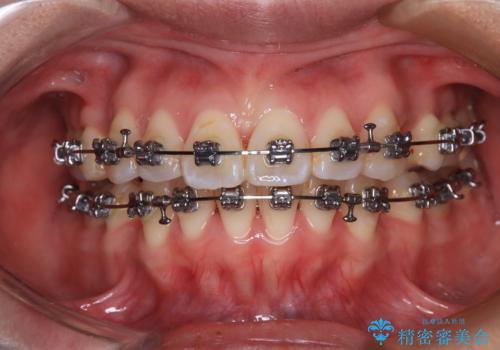

- 矯正装置

- メタルブラケット

- 上下の出っ歯を気にして来院された患者様です。

口元を積極的に引っ込めるために、上下左右の第一小臼歯を4本抜歯することとしました。

また、上下前歯は舌の突出癖による開咬となっていたため、舌のトレーニングを徹底するよう指示しました。